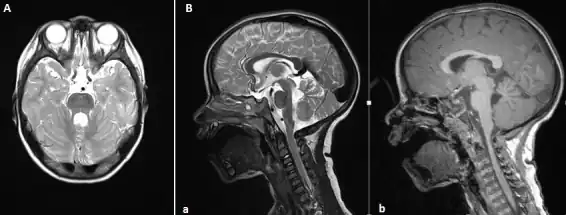

(A) MRI Brain, axial T2 sequence showing enlarged superior cerebellar peduncles and vermian hypoplasia resulting in characteristic "molar tooth" appearance; (B) MRI Brain, sagittal T2 (a) and T1 (b) sequences showing vermian hypoplasia, predominantly at the superior aspect

The disorder is characterized by the absence or underdevelopment of the cerebellar vermis and a malformed brain stem (molar tooth sign), both of which can be visualized on a transverse view of the head MRI scan.[19] Together with this sign, the diagnosis is based on the physical symptoms and genetic testing for mutations. If the gene mutations have been identified in a family member, prenatal or carrier diagnosis can be pursued.[6]